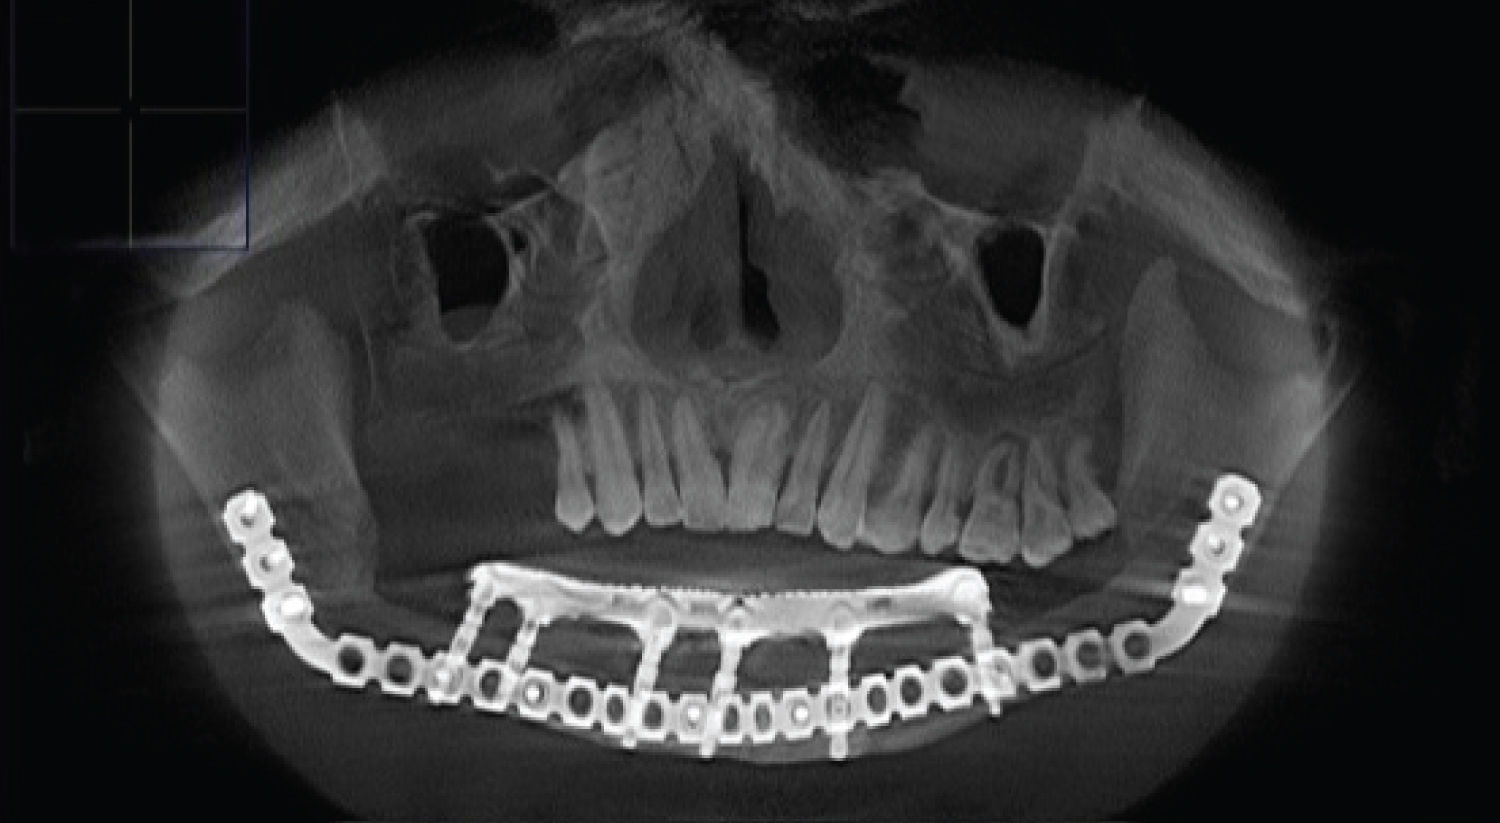

To assess the degree of osseointegration and determine the timing of the functional load of dental implants installed in free vascularized bone autografts, a Resonance-Frequency Analysis (RFA) of the stability of implants using Osstell Mentor (Osstell instrument, Integration Diagnostics AB, Gothenburg, Sweden) at time of implant placement, after 3 months. All patients presented functional and esthetic complaints. All patients underwent a thorough clinical laboratory, radiological examination according to a generally accepted scheme. Patients were evaluated by preoperative and postoperative outcome using computed tomography scan evaluation using CT Galileos (Sirona, German) (Figure 2, Figure 3, Figure 4, Figure 5 and Figure 6). Biopsy of the lesion was obtained in all cases. The choice of surgical treatment is determined by the type of lesions and the sizes of jaw defect.

Figure 6: (Patients 3) CT scan showed well integrated dental implants in fibula transplant after prosthetic rehabilitation. View Figure 6

Patients had received implant-bridge and hybrid denture that provided ideal facial balance and occlusion (Figure 5). The types of prostheses used varied among patients, depending on the need, occlusion and the number of implants that may be posted.

Radiograph was used to detect any bony abnormality and evaluate alveolar bone around each implant and made as average value. Postsurgical change in marginal bone level was assess by digital x-ray were taken immediately (base line for comparison) and 3 months after implant installation, after prosthesis loading, 1 year, 3 years, and 5 years after implant installation (Figure 5, Figure 6 and Figure 12).